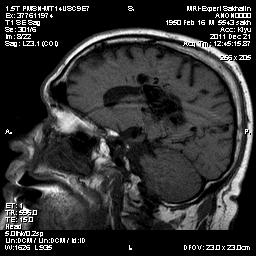

АВМ.

Случай моего коллеги.Публикую с его разрешения.

Направительный диагноз: последствия ОНМК в бассейне правой СМА (в 1984 года), правосторонний гемипарез.

Краткий анамнез заболевания, жалобы: беспокоит снижение чувствительности правой стороны туловища.